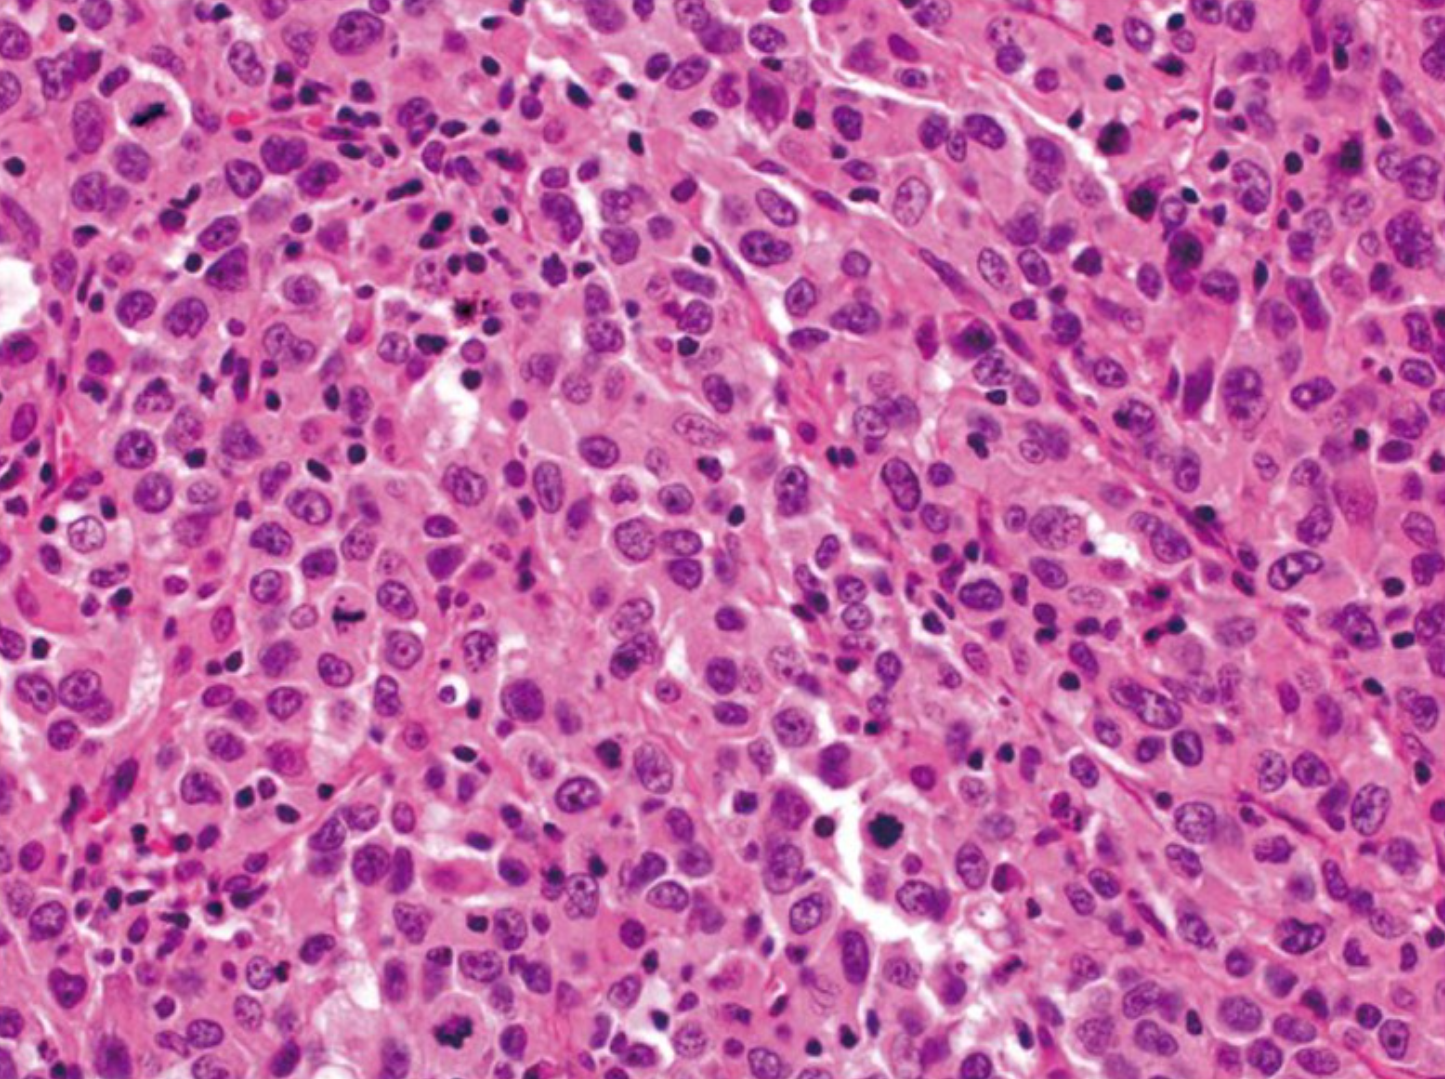

与胃相比,印戒细胞腺癌在结直肠中很少见,占所有结直肠癌的1%以下。 与黏液性癌相似,印戒细胞癌的定义是50%的肿瘤细胞表现出印戒细胞特征,其特征是胞浆内黏蛋白液泡突出,将细胞核推向外周(图4)。 印戒细胞可呈浸润性生长或存在于细胞外黏液池中。根据定义,印戒细胞癌是低分化的(高级别),其预后比传统腺癌更差 [4]。

若本图无法展示,请更换浏览器查看

图4.印戒细胞癌(放大原图×400) [4]。